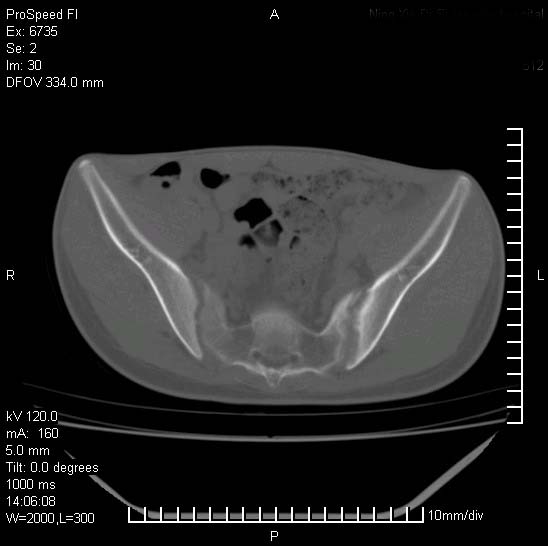

患者自诉胯部疼痛两年余,在当地服用中药,半月前至本院考虑骶髂关节结核,给予抗痨治疗。现发展至右下肢疼痛明显,活动受限,以膝关节处明显,拍膝关节平片无明显异常。

两侧骶骼关节改变,考虑强直性脊炎

左侧骶髂关节面限局性骨破坏,边缘硬化关节腔见钙化物;不出外tb

考虑强直性脊炎,建议查hla-b27

右侧骶髂关节也有类似改变,只是较左侧轻,首先考虑强直性脊柱炎,不除外结核,建议作hla-b27检查。

典型强脊炎改变,髋关节亦有累及

符合强直性脊柱炎表现。